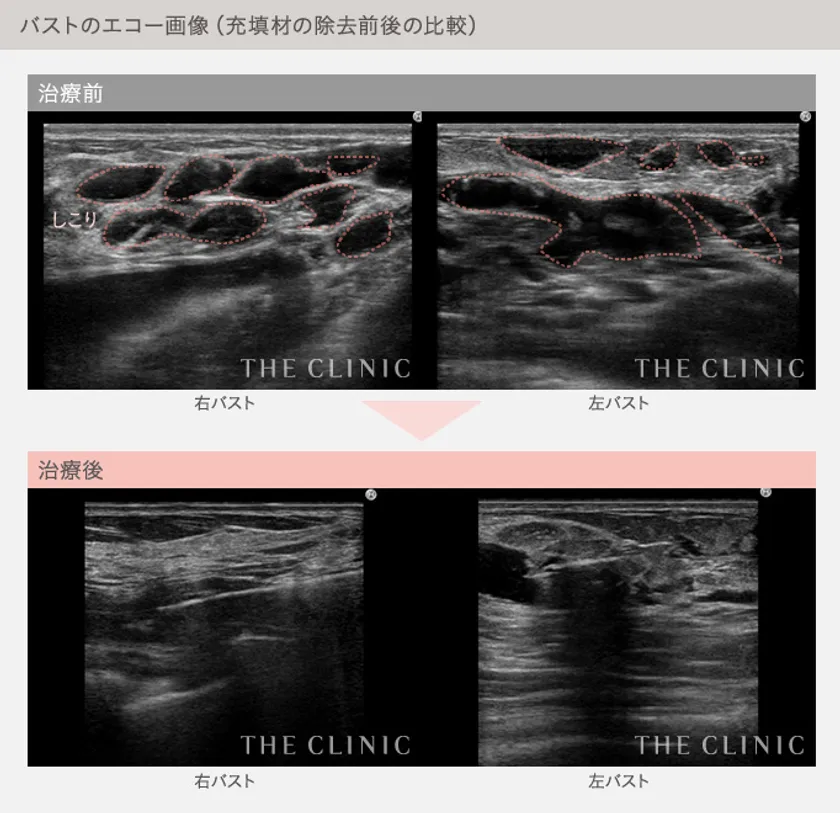

バストのエコー画像(充填剤の除去前後の比較)

豊胸後のバストのトラブルに対処する際、当院では必ずエコー検査を実施しています。エコー画像を通じてバストの内部がどうなっているかを的確に把握した上で、具体的な治療方針を決めていきます。

ジェル状充填剤による豊胸の失敗で最も多くみられる症状は「しこり」です。これに対しては、エコー画像でしこりの状態を確認してから、1つ1つ丁寧に除去していきます。除去する際には、生理食塩水やヒアルロニダーゼという酵素でしこりを柔らかくしながら、注射器で吸い出します。